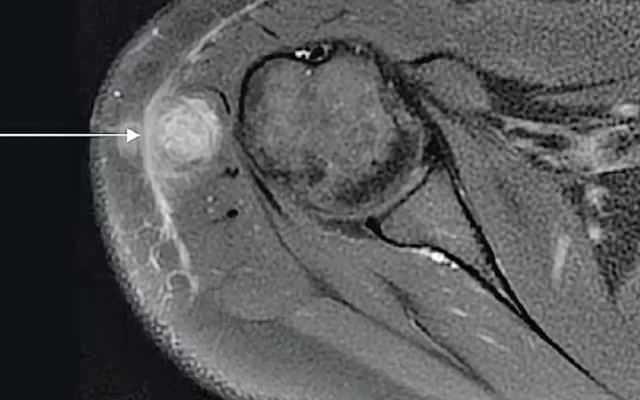

Yanlış aşı, bayanın kolunda iltihaplı bir apse oluşumuna sebep oldu. Yapılan testler sonrasında bu apsenin vereme neden olan bakteriler içerdiği ortaya çıktı.

Ayrıca, aşının deri altı yerine kas içine enjekte edildiği anlaşıldı. Bu da enfeksiyonun denetim edilemez formda ilerlemesine neden oldu.